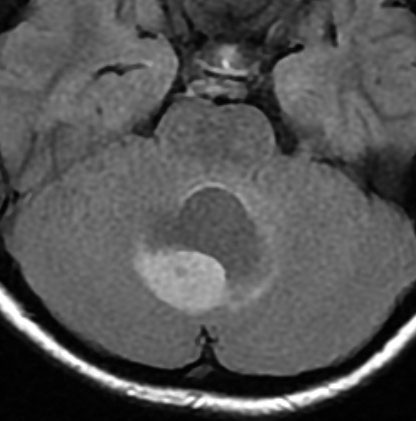

12歳の少女の小脳虫部と右半球深部白質の間にできた毛様細胞性星細胞腫 pilocytic astrocytoma です。軽い体幹失調がありました。のう胞壁の大部分には腫瘍はありませんが,一部に腫瘍壁があります。必ずしも境界は明瞭ではなく,小脳虫部の上内側面に広範囲に接着しています。年長児の毛様細胞性星細胞腫は,Rosental fiber, eosinophilic granular bodyが多く見られ,硬く,小脳脳組織に食い込み,簡単に剥離摘出できるものではありません。脳組織と切開切断するように切り落とさなければ全摘できないものです。

後頭下からみた腫瘍(緑)です。正中に大きな架橋静脈 vermian veinがあります。

この腫瘍を後頭下開頭で摘出しようとすれば,小脳虫部と右小脳半球の間をかなり長く縦切開しなければなりません。テント直下から小脳上面をたどっても腫瘍の上端は見えても摘出は不可能です。ですから,必然的にアプローチは後頭開頭経テント法 occipital transtentorial approachとなります。